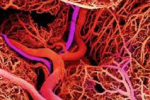

¿Sabías que las personas con Artritis Reumatoide tienen un mayor riesgo de enfermedades del corazón, en comparación con la población general?

La Artritis Reumatoide está vinculada a varios problemas cardiovasculares como la angina de pecho, infarto al miocardio y accidentes cerebrovasculares.

-Algunos investigadores creen que la inflamación de las articulaciones, provocada por la Artritis Reumatoide, hace que el corazón lata de manera irregular, una condición conocida como fibrilación auricular; la cual puede conducir a la formación de coágulos de sangre, que a su vez puede provocar un accidente cerebrovascular.

-Otros autores señalan que la activación inmune crónica y los mecanismos inflamatorios pueden desempeñar un papel importante en la insuficiencia cardiaca. Las personas con Artritis Reumatoide tienen niveles marcadamente elevados de mediadores de la inflamación como las citocinas y la proteína C-Reactiva, por lo que resulta alto el riesgo de la progresión de insuficiencia cardiaca y, en consecuencia, mayor mortalidad.